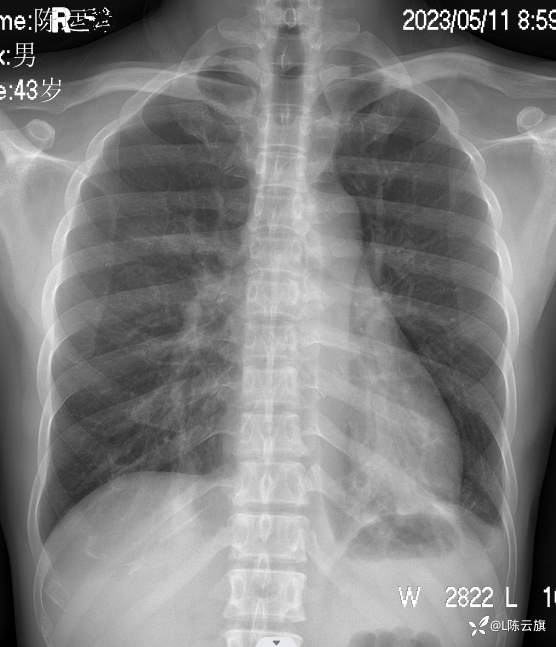

胸片2: